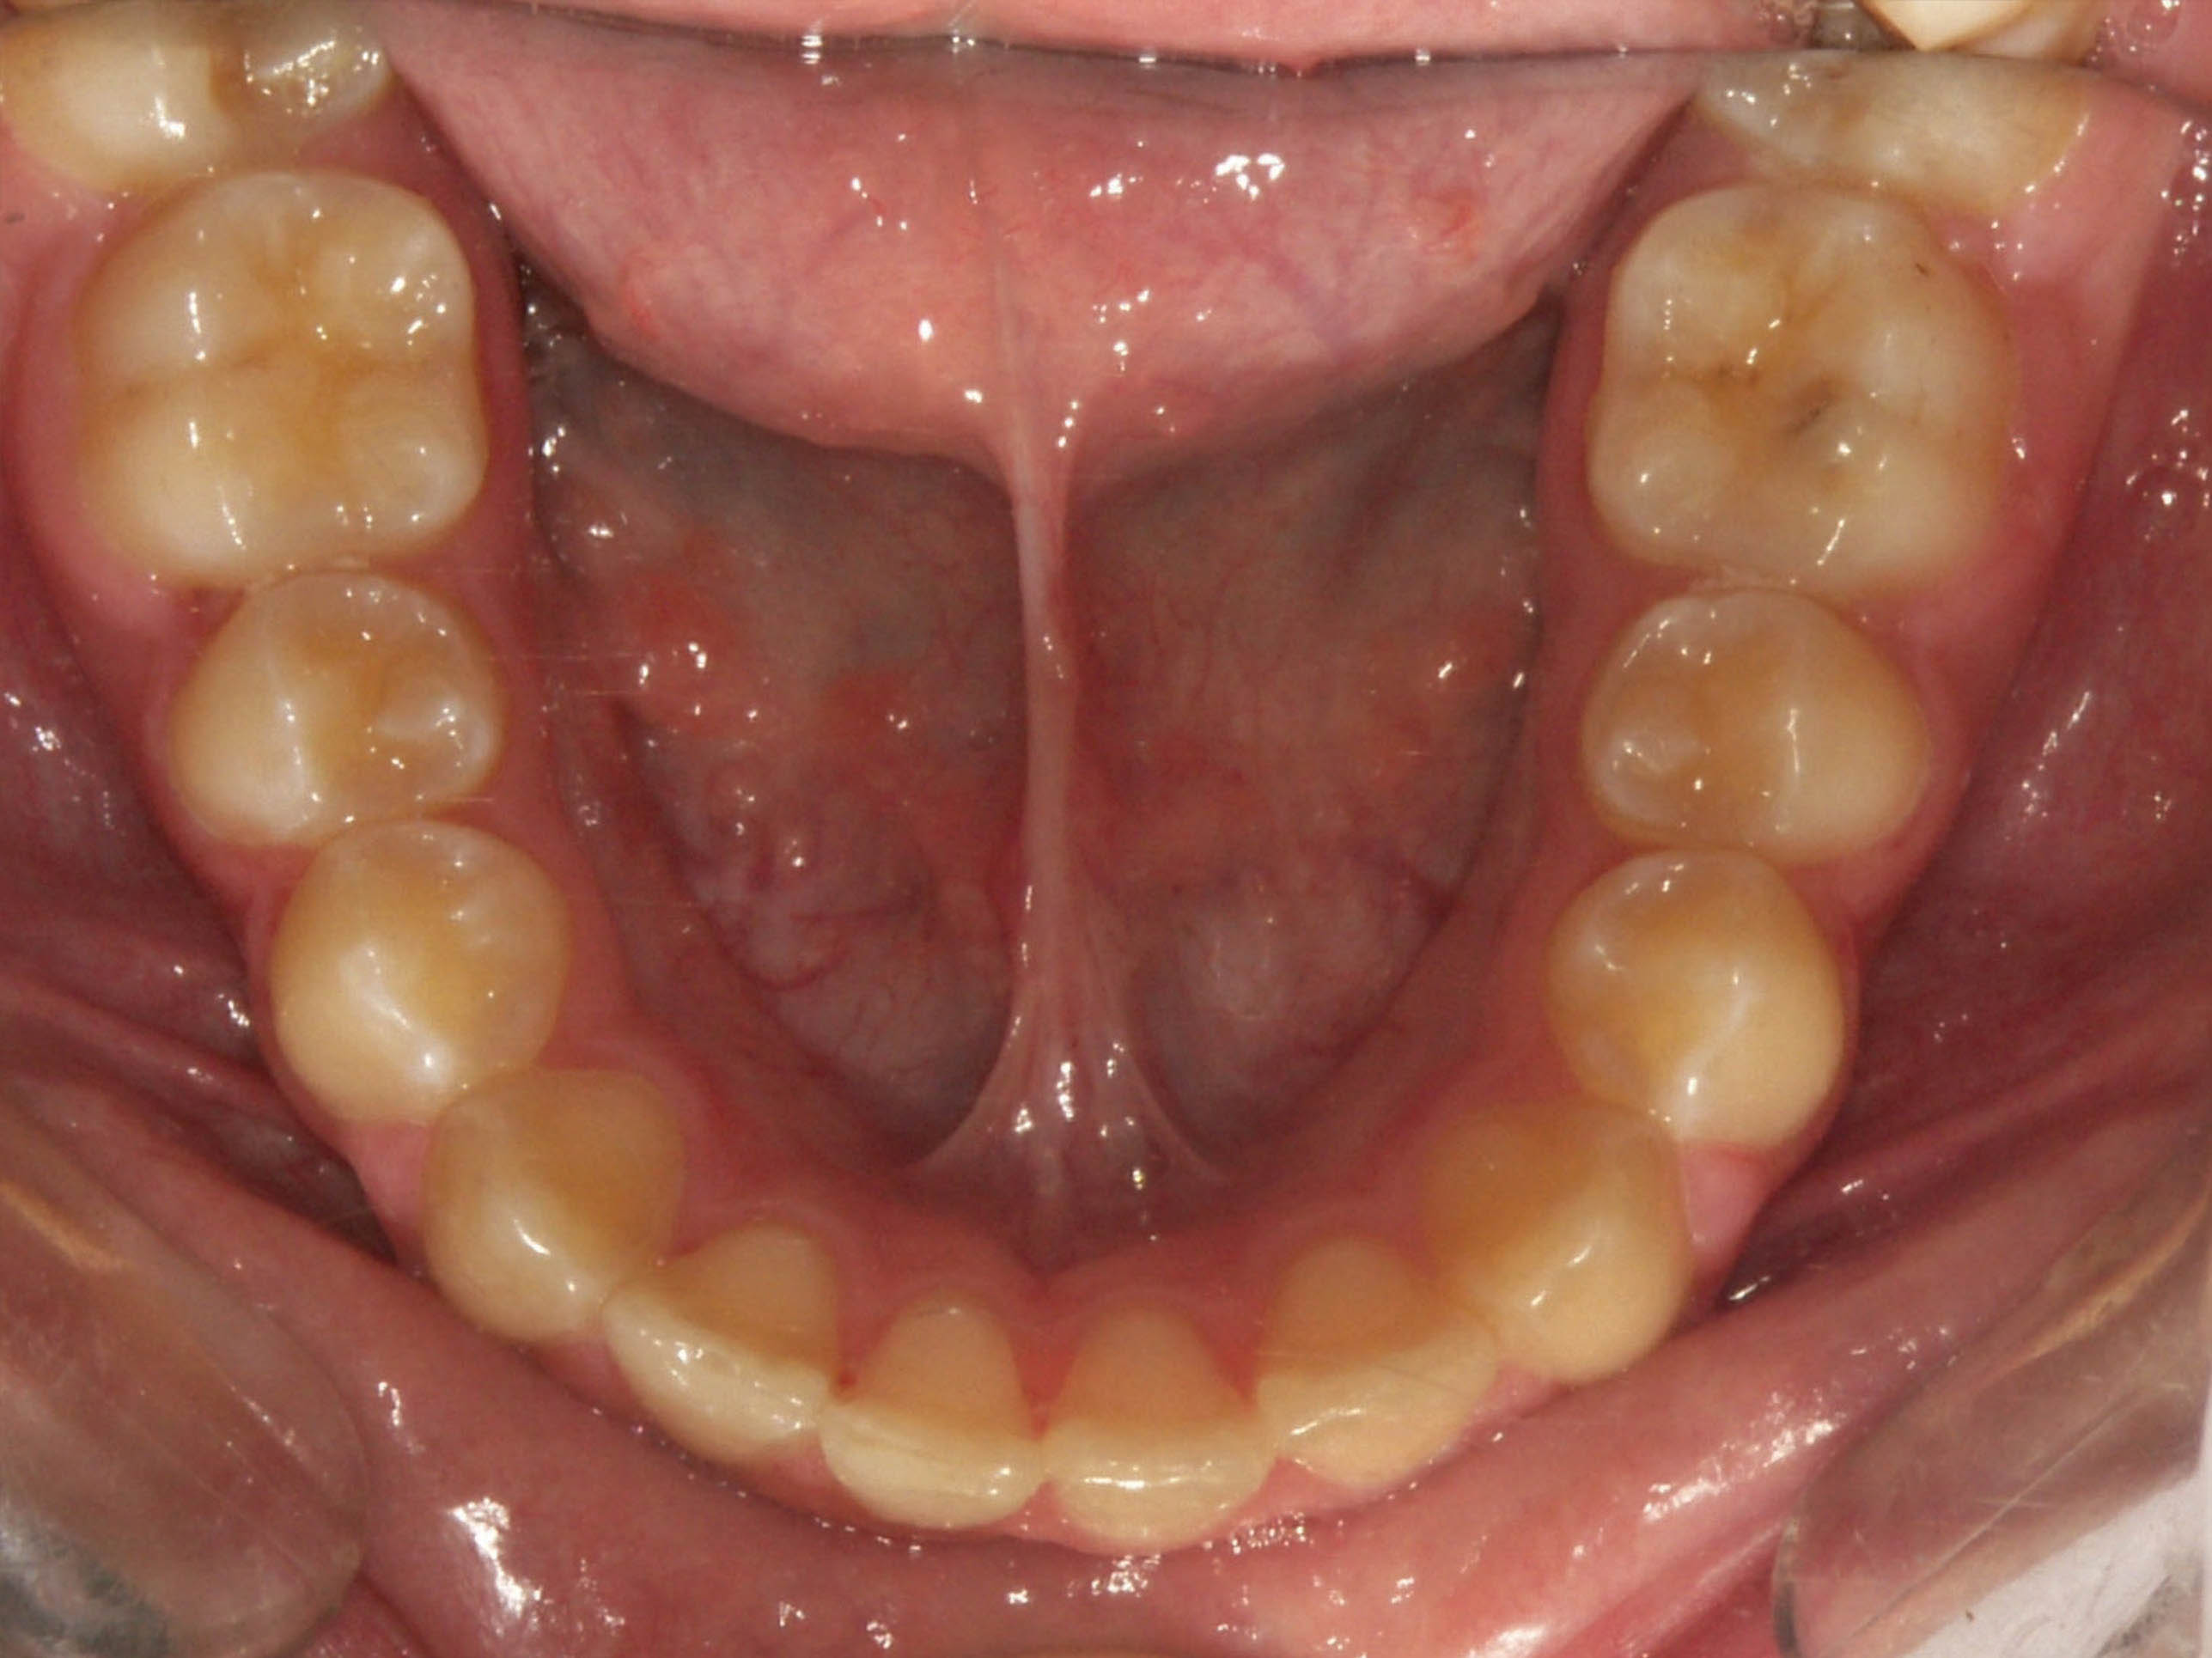

قبل از درمان